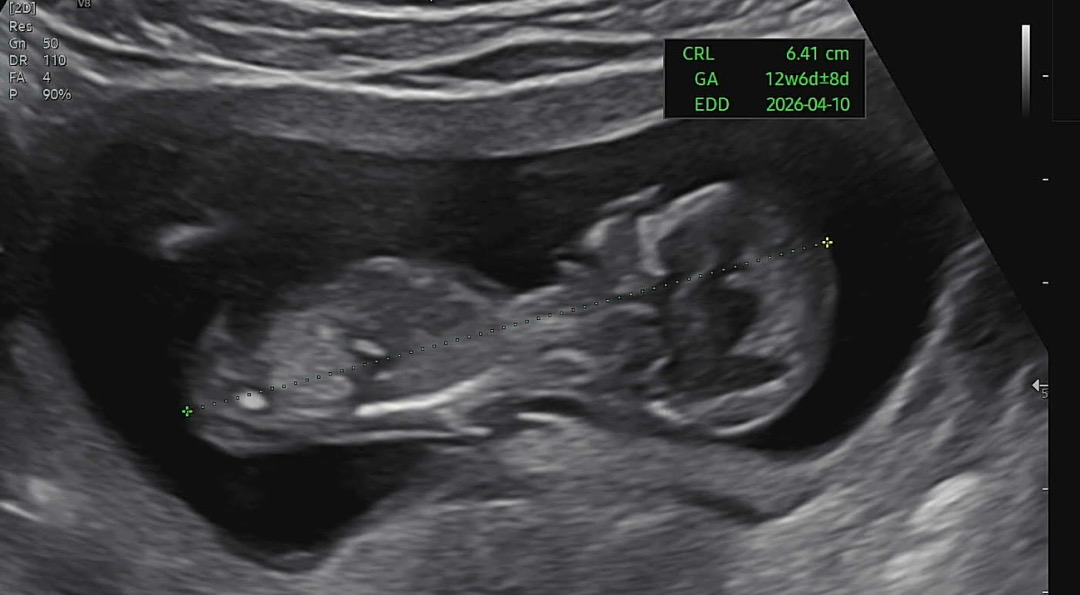

다들 어때보이세여..? 각도법 ㅎㅎ 👼

각도법으로 보기 힘들어 병원에서 최대한 알려드릴려고 했는데 ㅜㅜ 다리꼬고 엎두고 계속 움직여서 ㅜㅜ후…아무답도 못들었습니당..우리 배동 여러분 어때 보이시나여…🥲